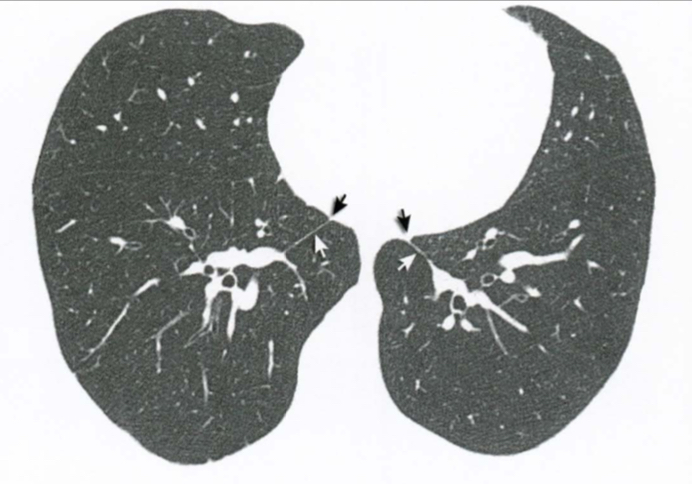

Qual a alteração demonstrada pelas setas?

Qual estrutura apontada?